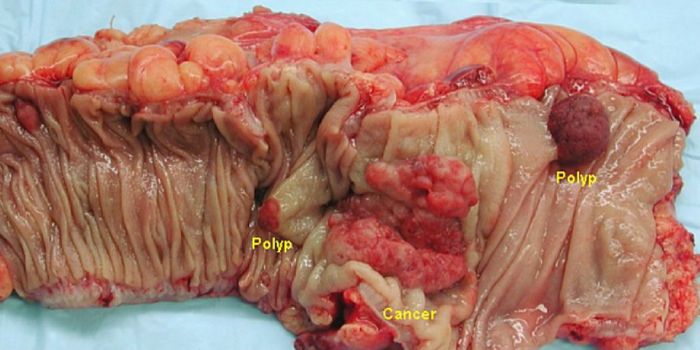

APR 13, 2017CancerThe onset of colon cancer may be tied to antibiotic use, reported scientists. The importance of the microbiome has only ...

AUG 04, 2022CancerStarch, a natural, sugar-containing component in many green plants, is present in high concentrations in foods such as p ...